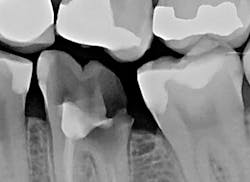

The patient presented with tooth No.19 ML with a history of endodontic treatment fractured to the level of the alveolus (figures 6-8). The patient had an inadequate clinical crown to restore. The options were either to extract the tooth and place an implant, or complete a crown lengthening and then restore. The clinical objective of crown lengthening was to establish biologic width and expose enough tooth structure coronal to the bone for a proper restoration. The patient opted for crown lengthening, and the procedure was completed in about 50 minutes.

Figure 6: Pre-op

Figure 7: Pre-op

Figure 8: Pre-op